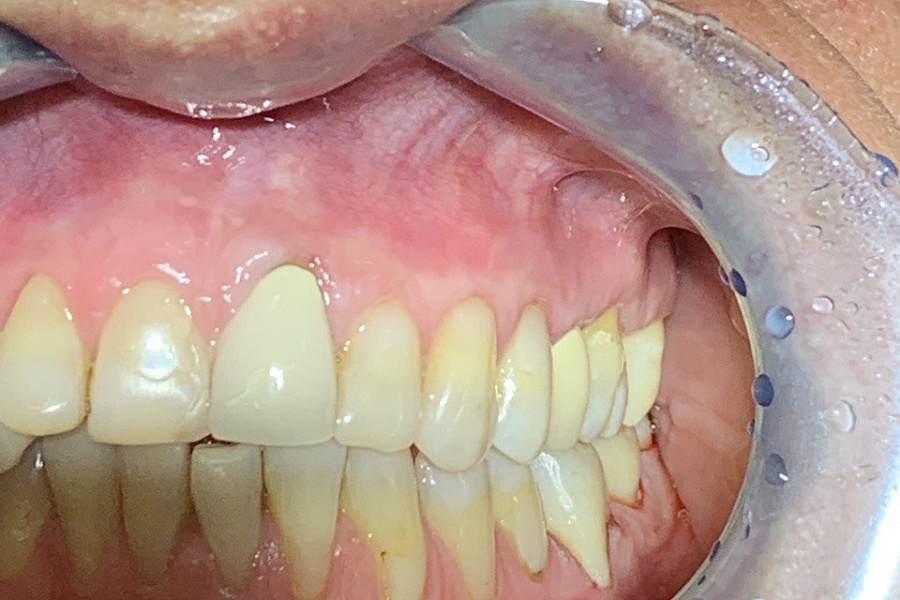

Пациент обратился в клинику с жалобами на оголение шеек и корней зубов, повышенную чувствительность зубов от холодного, горячего и других пищевых раздражителей, боли во время чистки зубов, косметический дефект.

Поставлен диагноз генерализованная рецессия десны в области зубов верхней и нижней челюстей, аномалии положения зубов